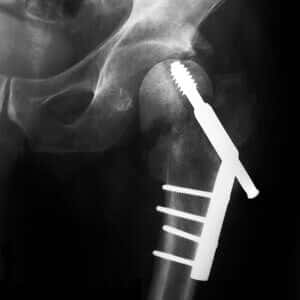

My doctor thinks these drugs are harmless, but I have read about problems with long-term use. I don’t need a broken bone at this stage of my life. Are there any natural approaches I could use while I try to get off Nexium?

A. Acid suppressing drugs such as Aciphex, Prevacid, Prilosec (omeprazole), Protonix or Nexium may produce unexpected complications. Articles in the Archives of Internal Medicine (May 10, 2010) have linked such drugs to an increased risk of fractures and infections (pneumonia and Clostridium difficile).